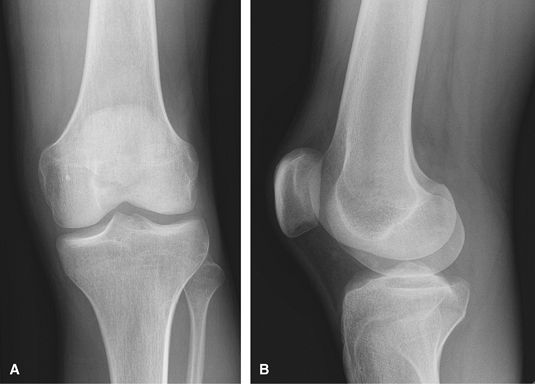

Knee

Nontrauma, Chronic Injury

Good for initial arthritis assessment. MRI is useful to

assess for internal derangement but is of less value when there is

obvious osteoarthrosis on radiographs.

![]() |

|

Figure 28 (A) AP. (B) Mediolateral lateral.